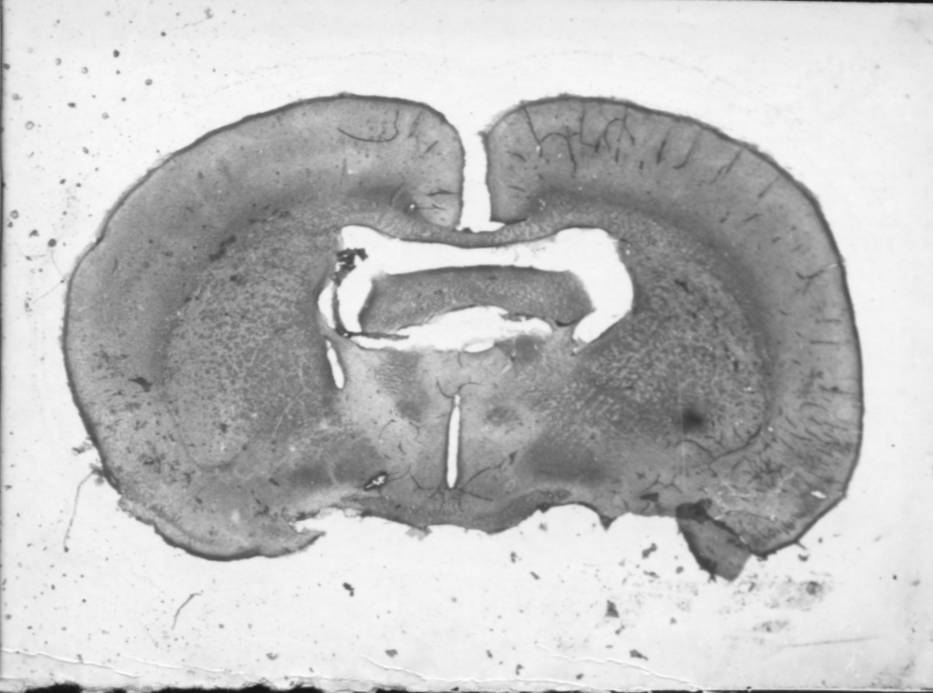

Рис. 2. Морфологическая картина зон микроинъекций веществ в центральное ядро миндалины (А) и ядро ложа конечной полоски (Б)

Координаты по атласу К. Кёнига и А. Клиппеля (1963). Показаны фронтальные срезы в мм относительно брегмы.